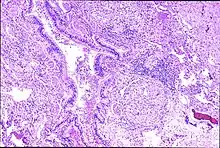

Peribronchal non-necrotizing granuloma from berylliosis

Granulomas are seen in other chronic diseases, such as tuberculosis and sarcoidosis, and it can occasionally be hard to distinguish berylliosis from these disorders. However, granulomas of chronic beryllium disease will typically be non-caseating, i.e. not characterized by necrosis and therefore not exhibiting a cheese-like appearance grossly.[5]